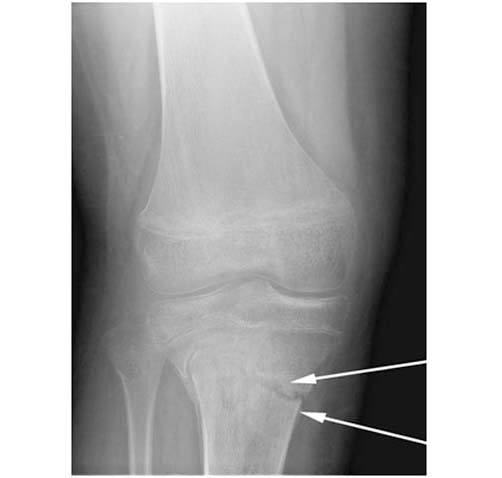

1.This xray at the time of the injury shows the fracture below the growth plate (white arrows)